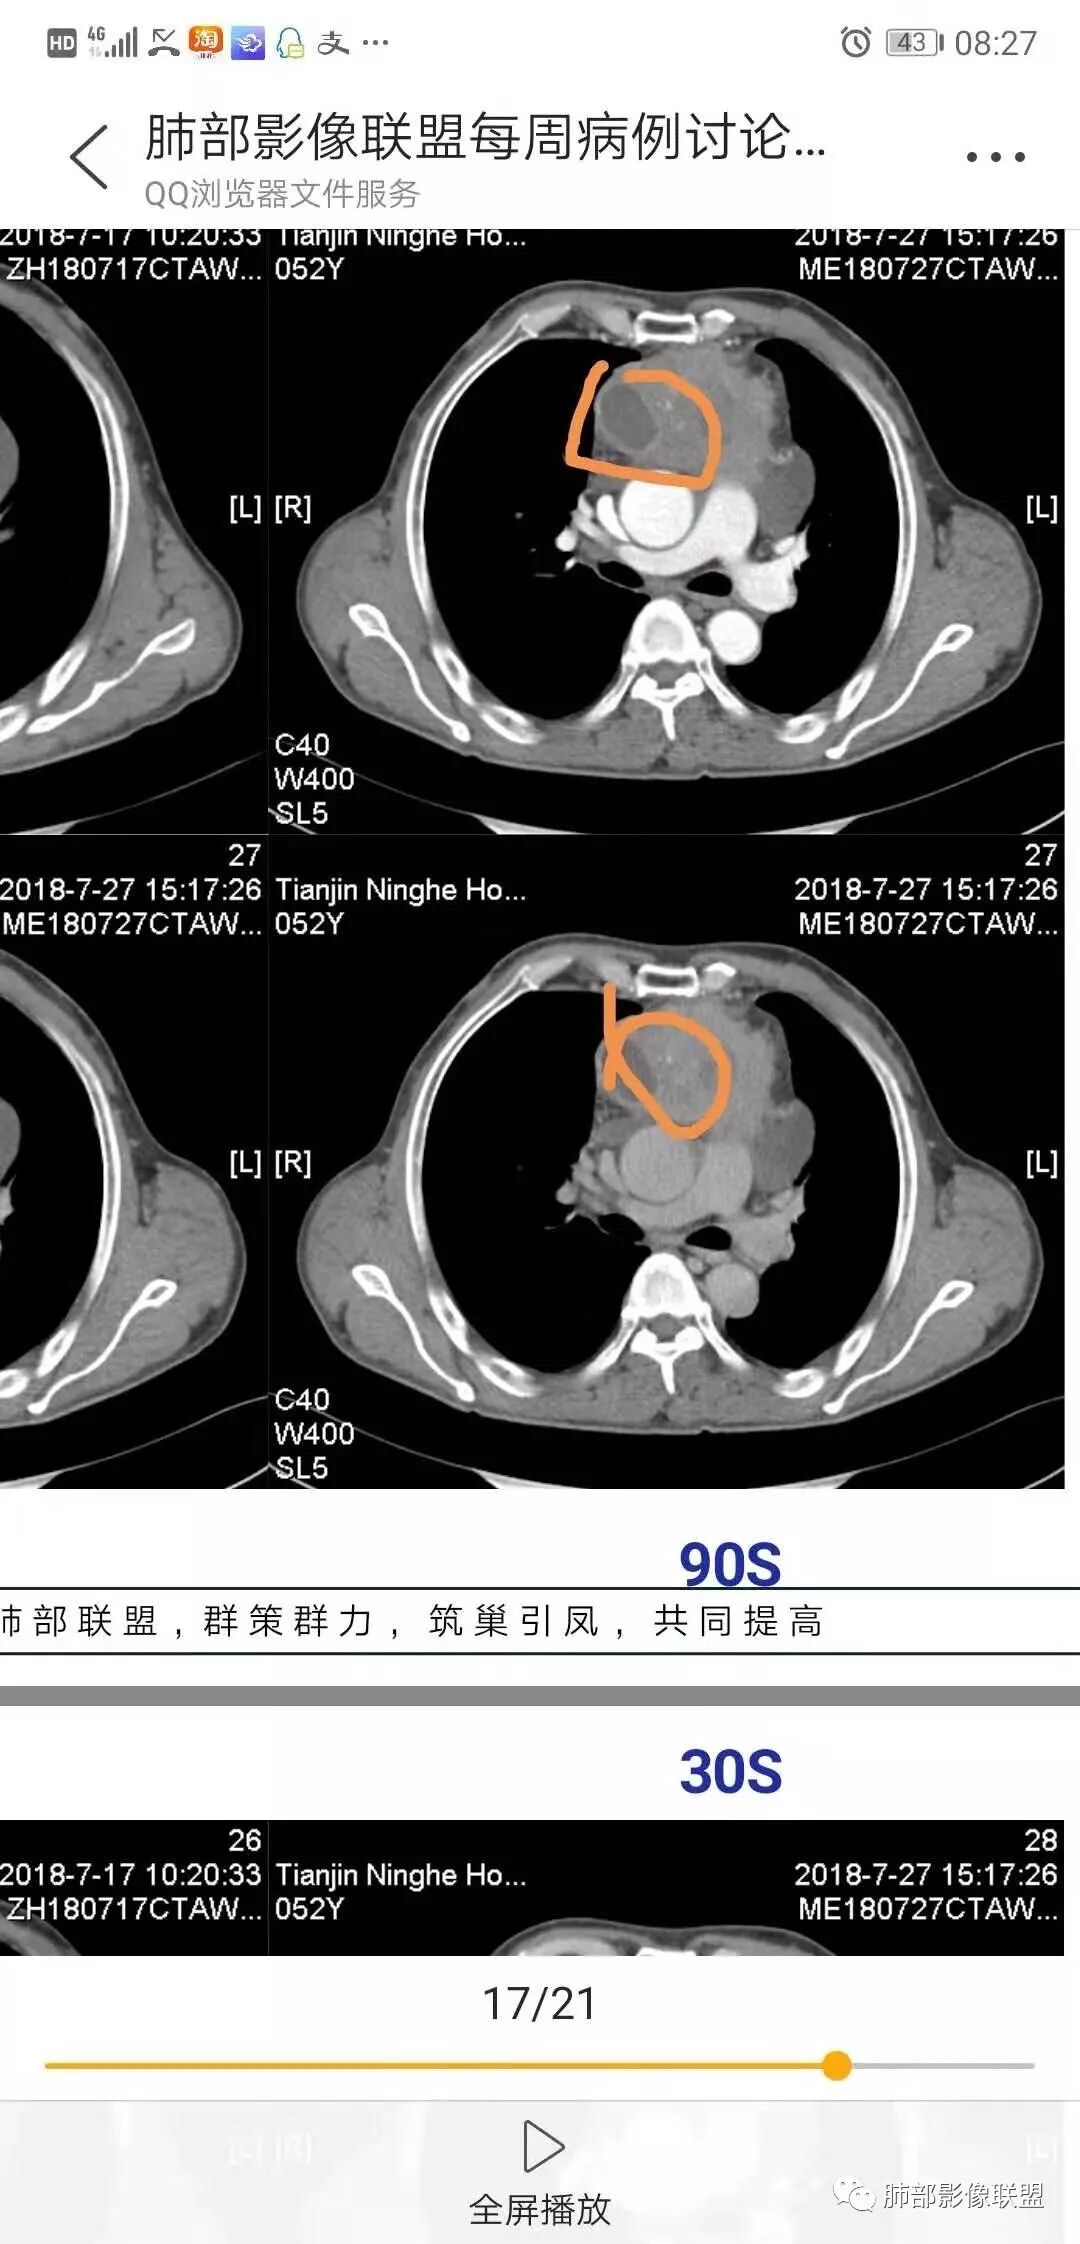

南边:强化就不用说了

大肿块,边缘不清,伴随肿大淋巴结,上腔静脉受侵犯——恶性

侵袭性胸腺瘤?胸腺癌?老年,钙化、肿大淋巴结,边缘侵犯、累及心包、侵犯上腔静脉——支持

b. ①纵隔脂肪间隙模糊、胸膜、心包侵犯、膈肌受累--见于高危胸腺瘤及胸腺癌,但是心包侵犯多见于B3胸腺瘤跟胸腺癌

②纵隔大血管侵犯、肺转移、膈神经麻痹、淋巴结转移及远处血行转移---多见于胸腺癌,B3胸腺瘤罕见

4.  纵隔淋巴结肿大及纵隔大血管(上腔静脉)受侵犯,提示胸腺癌或类癌。

结合临床表现患者应该存在左无名静脉明显侵犯,可惜未提供相应层面影像资料。

5. 此患者NSE增高,提示神经内分泌肿瘤可能,纵隔神经内分泌癌最常见的是不典型类癌,胸腺类癌临床上可伴相关临床表现。肿瘤体积巨大,边缘清晰,强化显著(与鳞癌不同),肿瘤内边缘规则的管状血管影(鳞癌内血管是破坏、纤细、僵硬);